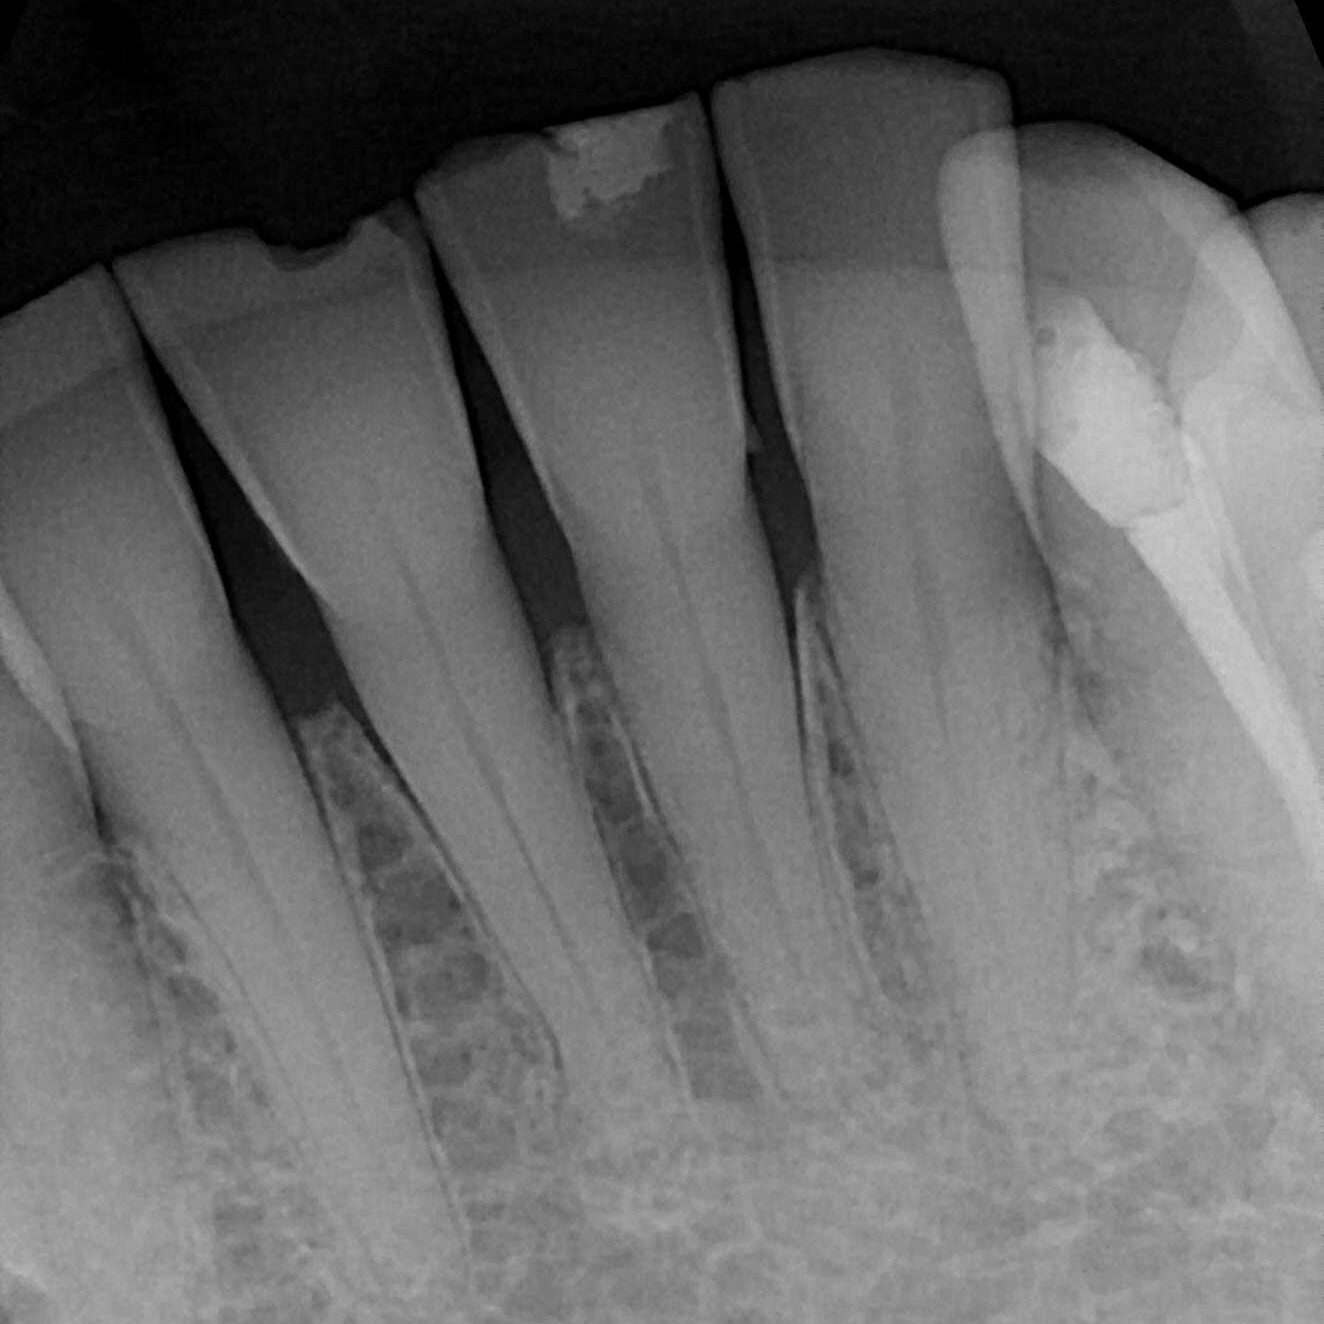

Chip

Chipped Tooth – how many of these do you see and repair without long-term success?